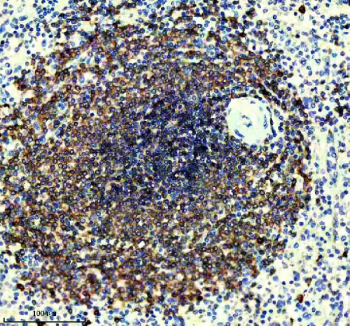

IHC staining of FFPE human spleen tissue with CD22 antibody, HRP-secondary and DAB substrate. HIER: boil tissue sections in pH8 EDTA for 20 min and allow to cool before testing.